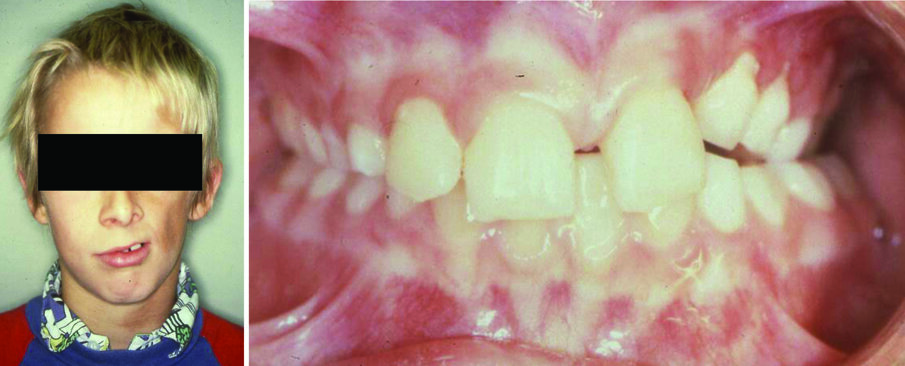

Facial disproportions could be the result of muscular and soft tissue asymmetry (e.g., hemifacial atrophy or cerebral palsy), muscle size disproportion in volume and/or tonicity (e.g., masseter hypertrophy, dermatomyositis (Figure 6), and neoplasms (Figure 7)). Abnormal muscle function often leads to skeletal deviations (2).

Figure 6. A 10-year-old boy with dermatomyositis creating a soft tissue tonicity imbalance (a) and resulting in a unilateral posterior crossbite (b).